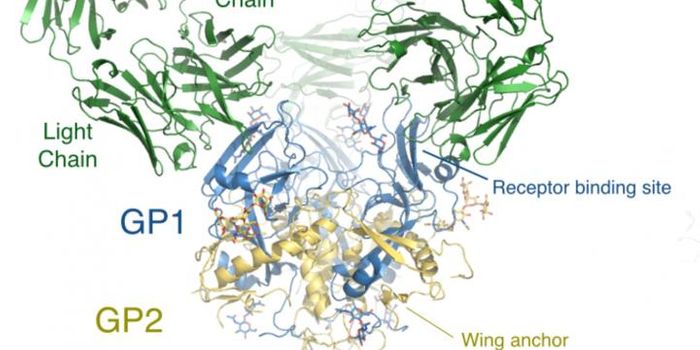

MAY 02, 2016ImmunologyFindings Could Guide Development of Treatments for Lassa Fever For the first time, scientists at The Scripps Research In ...